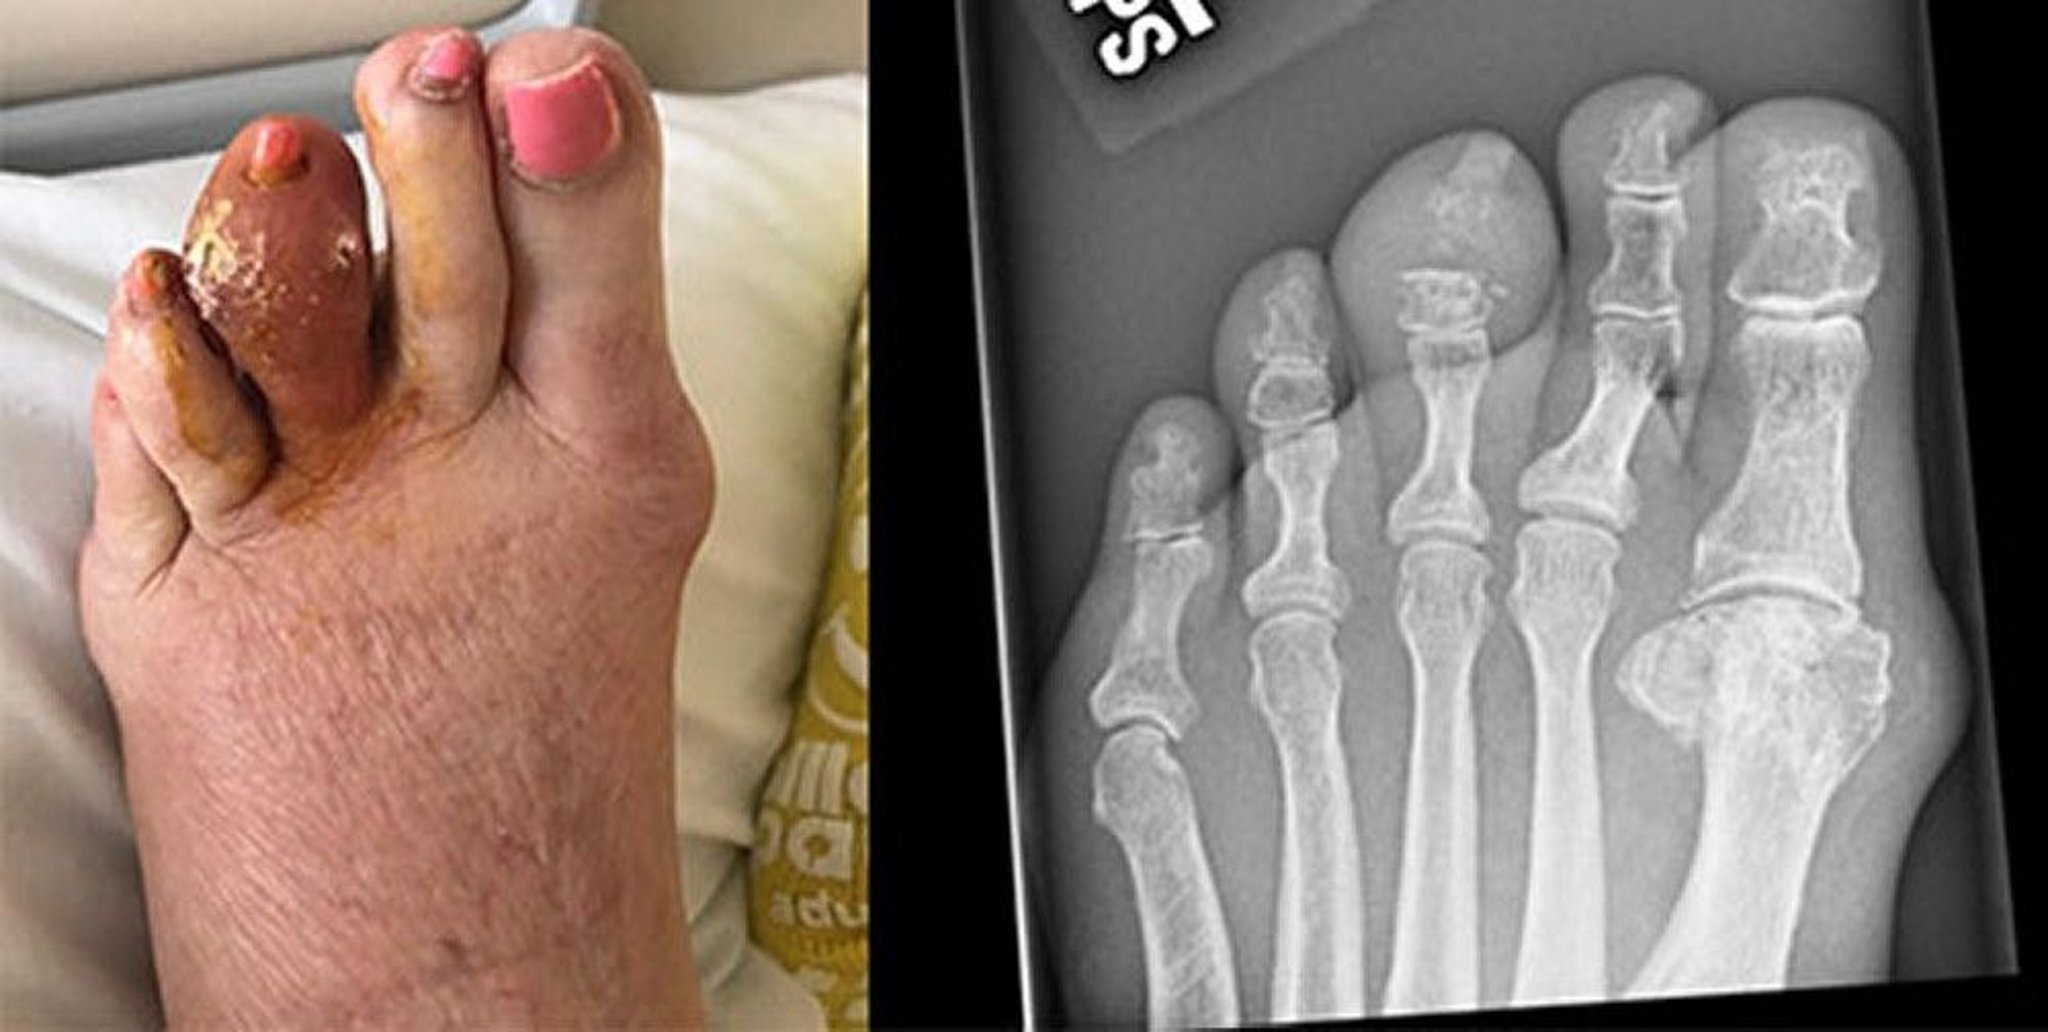

Gout of the Middle Toe

This photo shows a large tophus of the left third toe, which has broken down and released hardened uric acid. The radiograph on the right shows erosion of the middle phalanx and distal interphalangeal joint.

Images courtesy of Brian F. Mandell, MD.